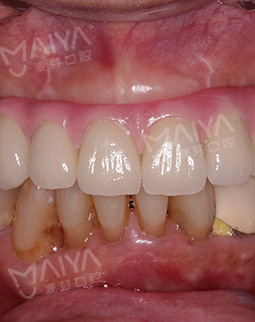

2019年4月15日 两个小时种好牙,一劳永逸享口福

今天来院种牙,肖阿姨满心欢喜地来到麦芽口腔,赵院长仅花了不到两个小时就为她种好了牙齿,种完牙后,肖阿姨竖起了大拇指:"种牙一点都不痛,打麻醉也很到位,用的针很小,我这么瘦都没什么感觉,胖一点更不会有。没有想象中可怕,整个过程很快,我也很放松,赵院长技术真的非常棒,术后没有不适感。"如今,肖阿姨看上去仿佛年轻了10岁,有了牙齿能够享口福了,生活也更加滋润。"现在有口福了,出去旅行才有意义。"说起种牙的愿望,肖阿姨说道。